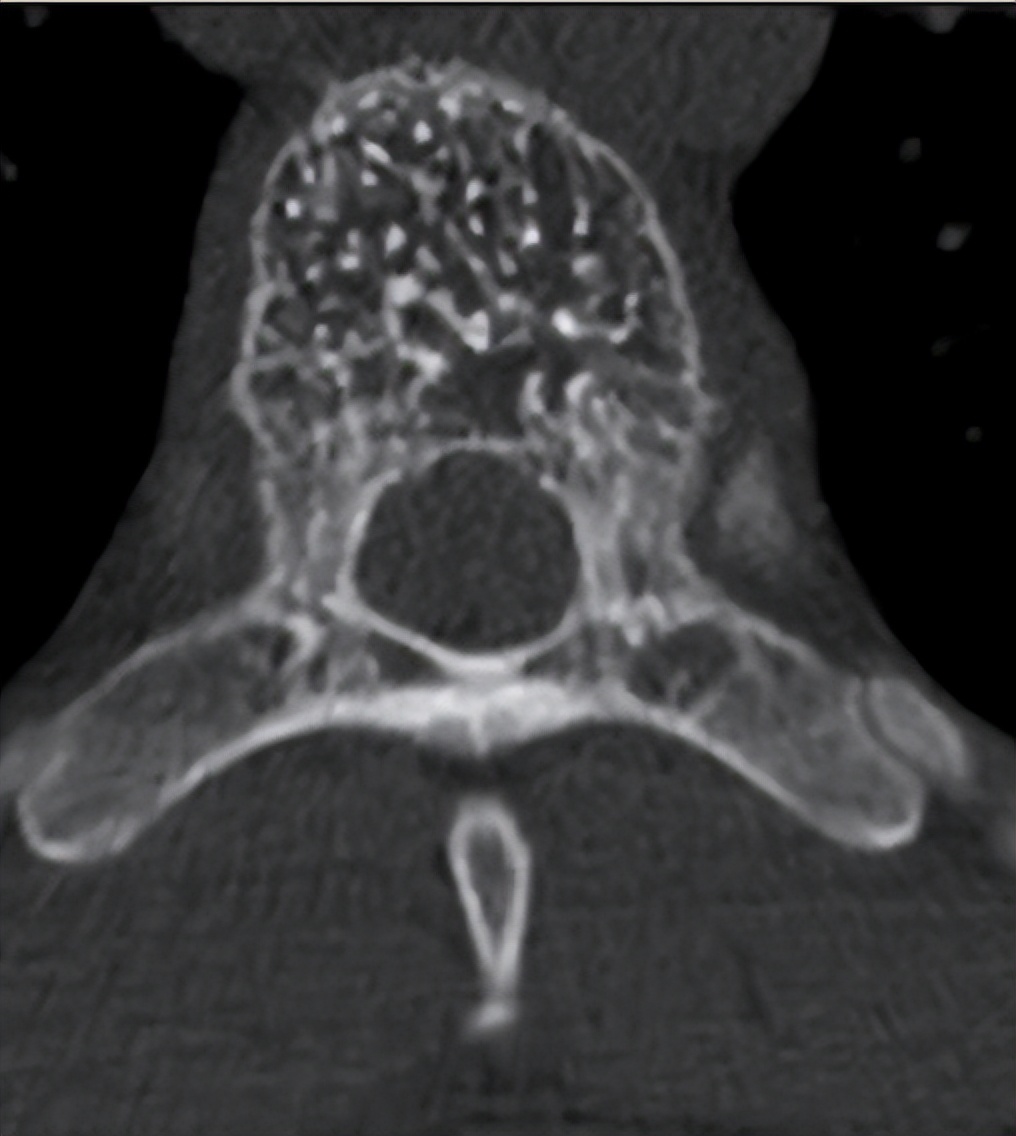

这是椎体血管瘤CT的典型表现,是不是感觉像满天星呢?医学上叫“栅栏样改变”